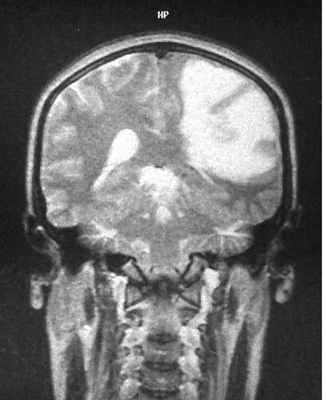

МРТ головного мозга. Анапластическая астроцитома. Корональные Т2-зависимая МРТ и Т1-зависимая МРТ с контрастированием.